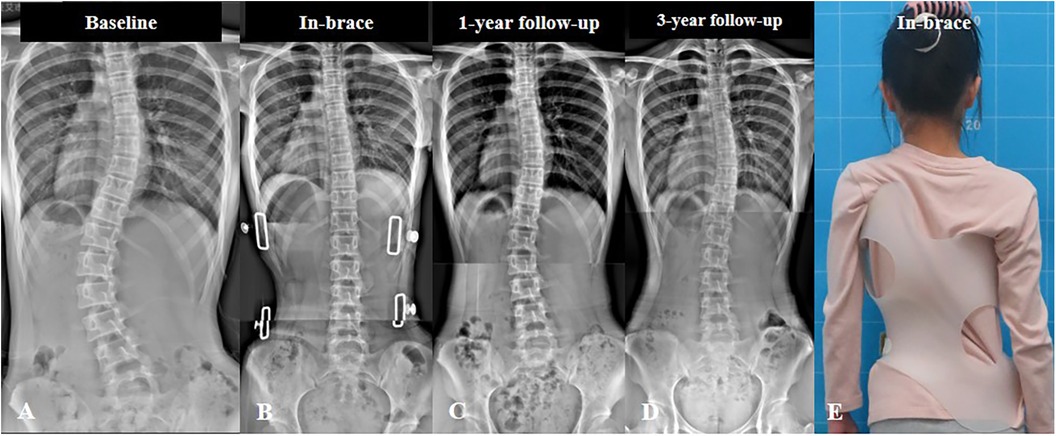

شارك في الدراسة 135 مراهقًا يعانون من جنف بسيط إلى متوسط، وكان لديهم انحناء أساسي للعمود الفقري بين 20° و40°. جميع المشاركين ارتدوا حزامًا طبيًا مخصصًا للظهر والصدر لمدة لا تقل عن سنة، وتمت متابعتهم حتى اكتمال نمو العظام لديهم.

قبل العلاج، كان متوسط الانحناء الأساسي للعمود الفقري في المجموعة الأولى 30.6°، وفي المجموعة الثانية 31.7°.

أثناء ارتداء الحزام، انخفض الانحناء إلى 22.9° و24.2° على التوالي.

المراهقين غير المكتمل نمو عظامهم يحتاجون أن يكون الانحناء داخل الحزام أقل من 25°، أما المكتملون فالأفضل أن يكون أقل من 30°.